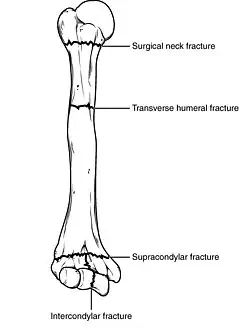

Types of major humerus fractures

Fractures of the humerus are classified based on the location of the fracture and then by the type of fracture. There are three locations that humerus fractures occur: at the proximal location, which is the top of the humerus near the shoulder, in the middle, which is at the shaft of the humerus, and the distal location, which is the bottom of the humerus near the elbow.[9] Proximal fractures are classified into one of four types of fractures based on the displacement of the greater tubercle, the lesser tubercle, the surgical neck, and the anatomical neck, which are the four parts of the proximal humerus, with fracture displacement being defined as at least one centimeter of separation or an angulation greater than 45 degrees. One-part fractures involve no displacement of any parts of the humerus, two-part fractures have one part displaced relative to the other three; three-part fractures have two displaced fragments, and four-part fractures have all fragments displaced from each other.[13][14][3] Fractures of the humerus shaft are subdivided into transverse fractures, spiral fractures, "butterfly" fractures, which are a combination of transverse and spiral fractures, and pathological fractures, which are fractures caused by medical conditions.[12] Distal fractures are split between supracondylar fractures, which are transverse fractures above the two condyles at the bottom of the humerus, and intercondylar fractures, which involve a T- or Y-shaped fracture that splits the condyles.[7]

Humerus fractures are among the most common of fractures. Proximal fractures make up 5% of all fractures and 25% of humerus fractures,[9] middle fractures about 60% of humerus fractures (12% of all fractures),[12] and distal fractures the remainder. Among proximal fractures, 80% are one-part, 10% are two-part, and the remaining 10% are three- and four-part.[22] The most common location of proximal fractures is at the surgical neck of the humerus.[3] Incidence of proximal fractures increases with age, with about 75% of cases occurring among people over the age of 60.[11] In this age group, about three times as many women as men experience a proximal fracture.[23] Middle fractures are also common among the elderly, but they frequently occur among physically active young adult men who experience physical trauma to the humerus.[12] Distal fractures are rare among adults, occurring primarily in children who experience physical trauma to the elbow region.[7]